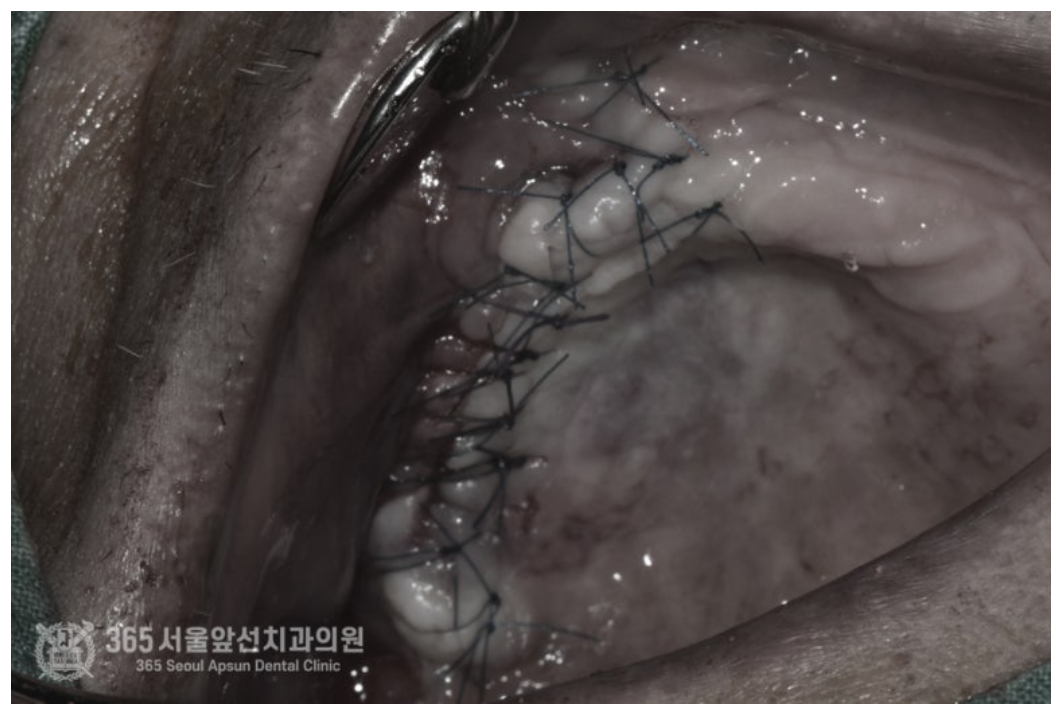

촬영일자 : 2024.07.05 구강상악동누공 폐쇄술을 시행한 직후 구강내 사진입니다. 누공의 크기가 매우 크고 내부의 염증으로 인해 상악동 점막과 구강점막이 엉켜붙어있어 이를 정리하며 수술을 시행했습니다. 수술과정에서 누공 부위 폐쇄를 위해 연조직을 늘리는 술식과 상악동 점막을 거상하며 골이식을 시행하는 작업까지 동시에 진행하여 추후 시행될 임플란트 식립까지 고려하여 한번에 수술을 마무리 해드렸습니다.